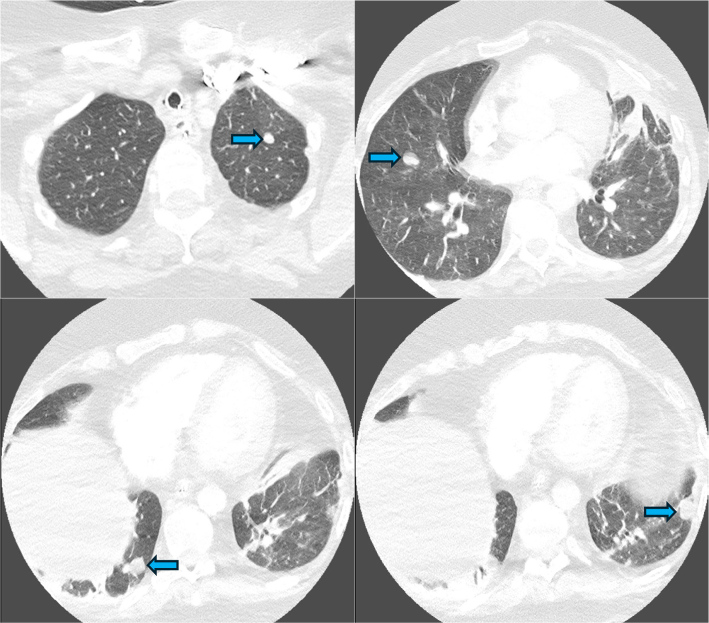

Guillain-Barré syndrome is an immune-mediated neuropathy characterised by acute-onset of symmetric, ascending motor weakness and areflexia. Acute motor axonal neuropathy, a severe axonal variant, is distinguished by direct axonal injury and poor functional recovery. Although infections are recognised triggers for Guillain-Barré syndrome, it is notable that up to half of cases occur without a preceding infectious event, suggesting that other factors such as underlying malignancy may contribute to disease onset. We present a rare and fatal case of acute motor axonal neuropathy in a 70-year-old woman, who was ultimately found to have an underlying pleomorphic liposarcoma. The patient presented with one week of progressive weakness, fatigue and encephalopathy. She required urgent mechanical ventilation due to respiratory failure; imaging identified multiple bilateral pulmonary nodules. Neurologic evaluation confirmed acute motor axonal neuropathy through nerve conduction studies and cerebrospinal fluid analysis, which showed albuminocytologic dissociation and positive anti-GM1 IgG antibodies. Despite standard treatment with intravenous immunoglobulin, the patient experienced no neurological recovery. Further imaging revealed a large pelvic mass, that was not present on a scan performed two months earlier. A biopsy confirmed pleomorphic liposarcoma, a rare and aggressive soft tissue sarcoma. Paraneoplastic panel testing was negative for onconeural antibodies, yet the clinical context raised suspicion for an immune-mediated, tumour-associated neuropathy. Clinicians should maintain a high level of suspicion of underlying malignancy in patients with Guillain-Barré syndrome, especially in the absence of preceding infection and with rapid neurological decline.